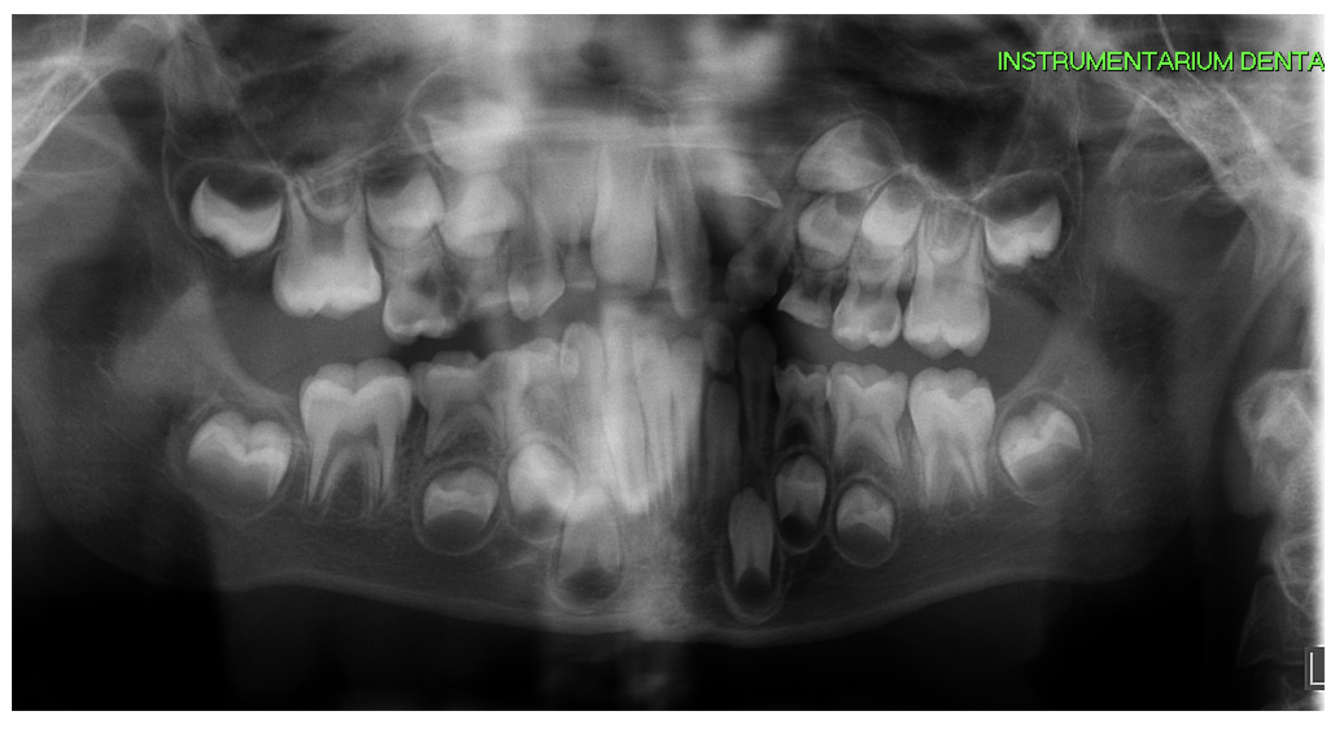

* 8 year old patient * Mom concerned about the extra tooth and child concerned about her teeth appearance * She has type 1 diabetes takes insulin injections (well controlled) From radiograph - caries present What management options can **you** provide for this patient? (4)

* Attempt caries removal for carious lesions on 55,54,64,74,85 and restore with composite, GI , RMGI (need compliance) * If not cooperative enough = SCC of 5's and 4's * If still not cooperative = SDF or non-restorative cavity control to make lesions cleansable * If not cooperative at all = Provide OHI and monitor or sedation under IS or GA

83

* 8 year old patient * Mom concerned about the extra tooth and child concerned about her teeth appearance * She has type 1 diabetes takes insulin injections (well controlled) From radiograph - caries present on primary teeth What treatment can you provide under LA?

* Selective caries removal (possible without)

84

* 8 year old patient * Mom concerned about the extra tooth and child concerned about her teeth appearance * She has type 1 diabetes takes insulin injections (well controlled) From radiograph - caries present What treatment options should be considered for GA?

* Surgical XLA of supernumeraries